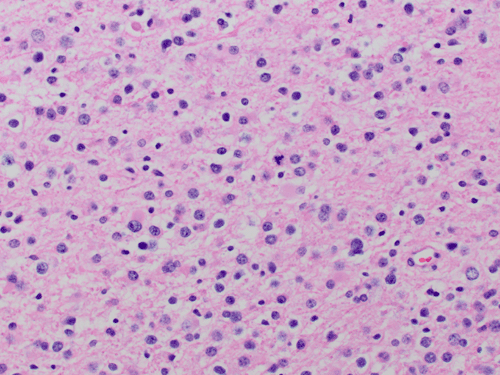

The some parts of the permanent sections (Panel C and D), there is higher cellularity in comparison to the frozen section. One should note that the cellularity of the tumor did not change. Freezing the tissue generates many large ice crystals and gives the bubbly or spongiotic appearance of glioma on frozen section (Panel B). During formalin fixation, the tumor shrink. With the same number of nuclei present, the permanent section always look more cellular than the frozen section in glioma. Also, the large bubbly look now becomes fine spongiotic change.

On the permanent sections, there is a significant variation in the cellularity. In focal area with high cellularity, the overall variation in nuclear size and shape are most consistent with an astrocytic tumor (Panel C) but focal areas with perinuclear halo (Panel D). Note that a mixed pattern of large, atypical nuclei and small nuclei without atypia is present. Mitotic figures are present (Panel D). Subpial extension of tumor cells (Scherer phenomenon) is also present (Panel E). Although not entirely specific, Scherer phenomenon is a strong suggestion of an infiltrating glioma. Endothelial proliferation or necrosis are not found but mitoses are more than occasional (Panel D). There is also one possible mitotic figure in the frozen section. Can you both of  them? With the nuclear atypia in the more cellular area and the presence of mitosis, the absence of endothelial proliferation, this is most consistent with a WHO grade III glioma. Although the focal perinuclear halo may suggest an oligodendroglial tumor, it is focal and not very classic. You can see this type of changes in an astrocytoma. In addition, this case does not show co-deletion of chromosome 1p and 19q. With all of these taken into consideration, this tumor is best diagnosed as an anaplastic astrocytoma, WHO grade III.